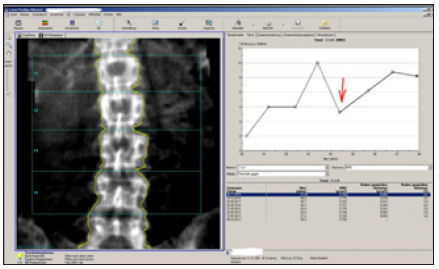

Patient A started DMAB treatment in 03/2012 at the age of 61 years. With a T-score at the lumbar spine of -3.9SD (BMD 0.708g/cm²) and a femoral neck fracture of the mother, there was a strongly increased risk of a 10-year fracture. Vitamin D was <5.0µg/l, the other values of the basic osteological laboratory were normal. Until 06/2015 there was an increase in BMD of +9.8% (+3.26% p.a.). Between the 7th and 8th DMAB- injection, the injection interval was exceeded for 4 months. The DXA control 06/2016 Figure 11 shows a loss of -6.2% (BMD -0.048g/cm²; LSC=0.028g/cm²). Fortunately, fractures did not occur.

Figure 11: